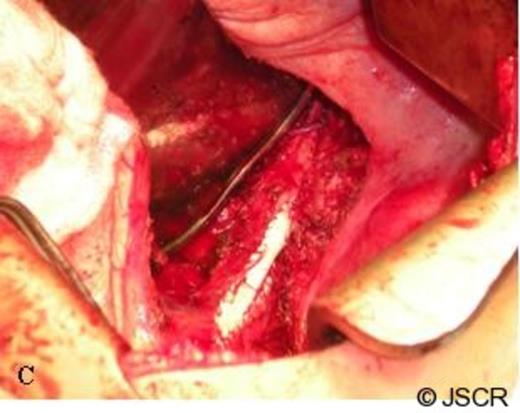

Following careful dissection of the posterior ligamentous attachments of the IVC to the liver, a Satinsky vascular clamp was placed and a 1 cm x 1 cm x 0.5 cm portion of the IVC was excised. The entire specimen was removed en bloc (Figure 2) consisting of diaphragm, right adrenal metastasis measuring 6 cm x 4 cm x 3 cm, a scant amount of normal adrenal tissue, the small patch of IVC and the right adrenal vein which was completely encased by tumor. A patch angioplasty of the IVC was then completed with a PTFE patch and sewn in with a running 5-0 Prolene suture (Figure 3). The diaphragm was closed primarily with pledgeted 1-0 Ethibond mattressed sutures, two 28-French chest tubes were placed through separate stab incisions, and the lung was re-expanded under direct vision. The patient tolerated the procedure well and was discharged home on post-operative day 8.